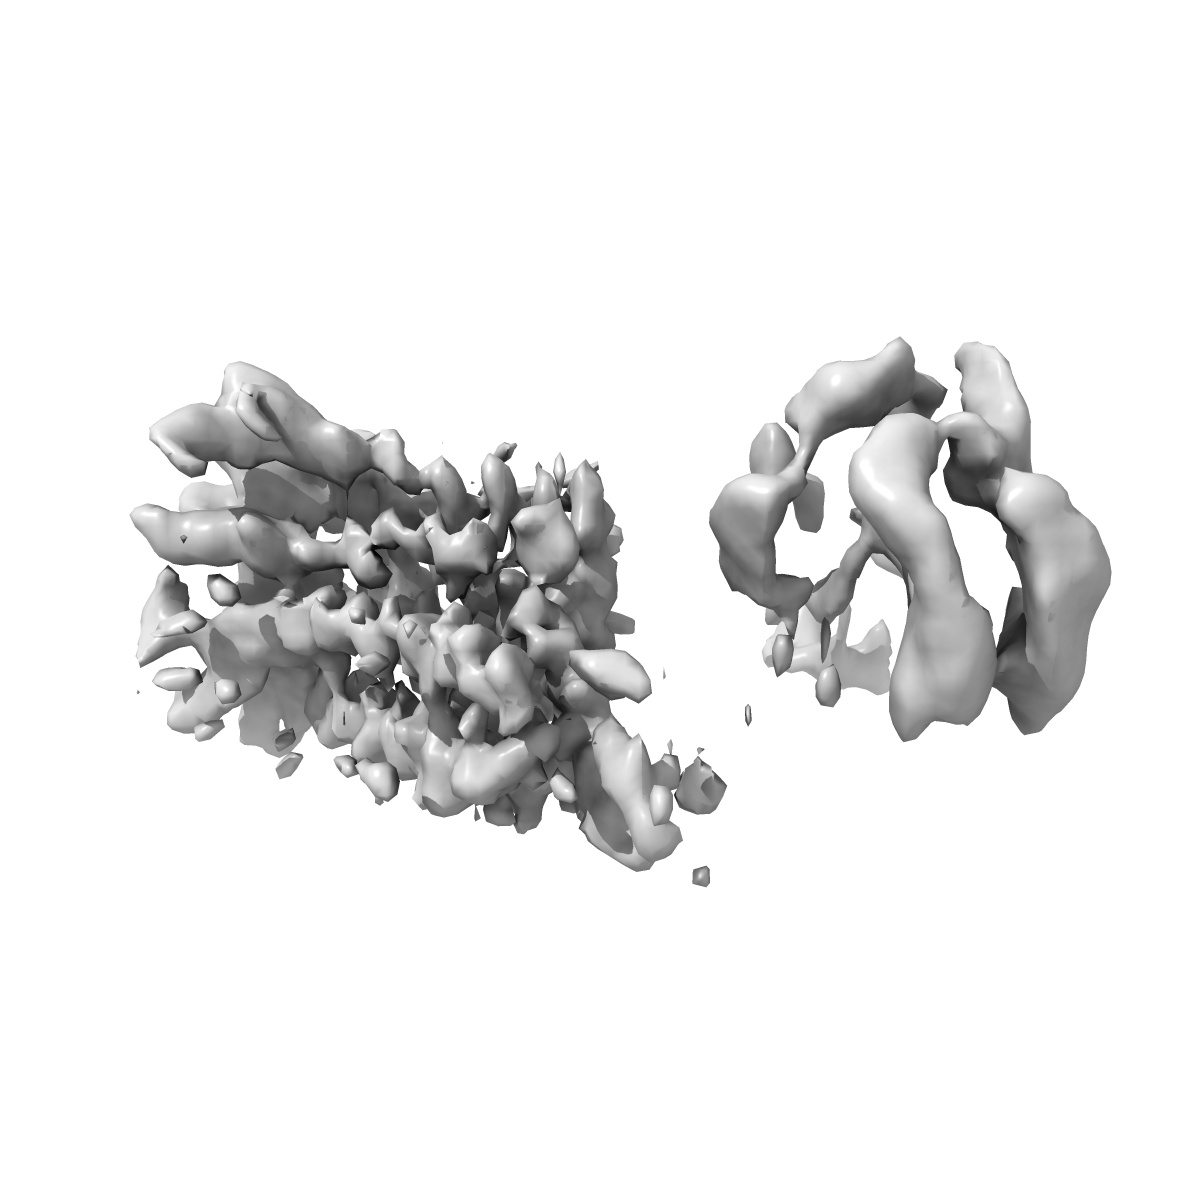

Kappa opioid receptor:Galphai protein in complex with inverse agonist norBNI, Original map receptor

Sample: Kappa opioid receptor in complex with heterotrimeric G protein (Gai/b/g) and inverse agonist norBNI

Structural basis of inverse agonism via inactive kappa opioid receptor:G protein complexes